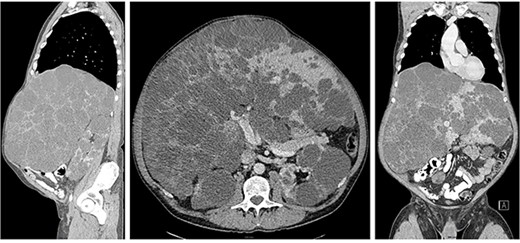

Liver transplantation was performed on 11th of July 2022: massive hepatomegaly (Fig. 2) and extensive adhesions due to previous laparotomy and inicisional hernia repair made the release of the recipient’s liver very difficult. The duration of the operation was 413 minutes, the anhepatic time was 73 minutes, and the cold ischemia of the donor liver was 517 minutes. In the final histology, the liver measures were 53 x 37 x 39 x 16 cm and weight 14,75 kg (Fig. 3). Histologically, it was an adult polycystic kidney disease with liver involvement (polycystic liver disease), there were no signs of malignancy.

The final pathology revealed the liver measures 53 x 37 x 39 x 16 cm and weight 14,75 kg.